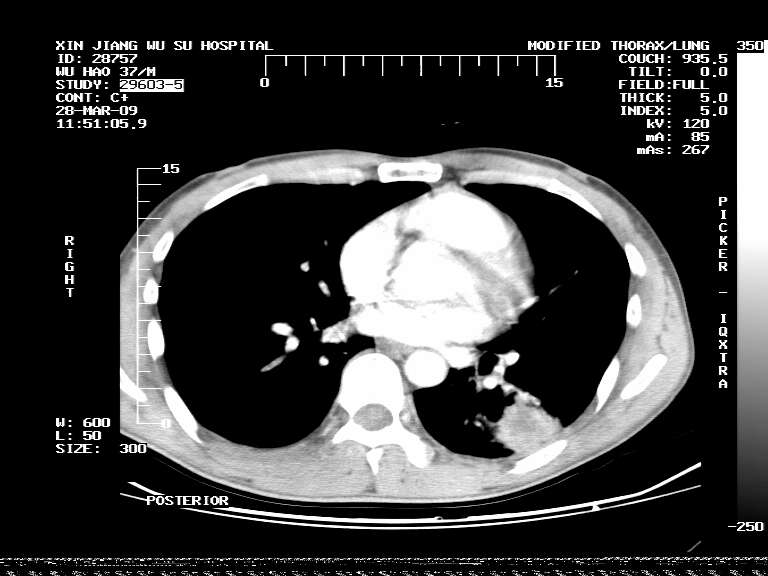

男,37岁,体检胸透发现阴影。

患者体检发现 无症状 左肺下叶占位,边缘模糊,可见血管聚束、分叶、胸膜牵拉,增强呈不均匀性强化。 首先考虑左肺下叶周围型肺癌,建议穿刺活检。

左肺下叶见一结节病变,边缘欠清不光滑,与胸膜粘连且胸膜局限性增厚,注药后呈环形强化,动脉期壁呈明显点环状强化,静脉期壁强化减低,中心密度低无强化,灶周无明显的卫星灶和水肿区(晕征)---考虑周围性肺癌,不除外感染性病变,建议穿刺活检。

左肺下叶软组织病灶,密度较高,内见点状钙化,其周围见子灶,邻近胸膜扁平样增厚.c+病灶强化明显,中心强化弱.诊断:左肺下叶结核瘤.

左肺下叶大片实变影,内靠胸膜见不规则更高密度结节灶,边缘强化,相邻胸膜增厚,胸膜下脂肪线存在。考虑炎症,结核可能。